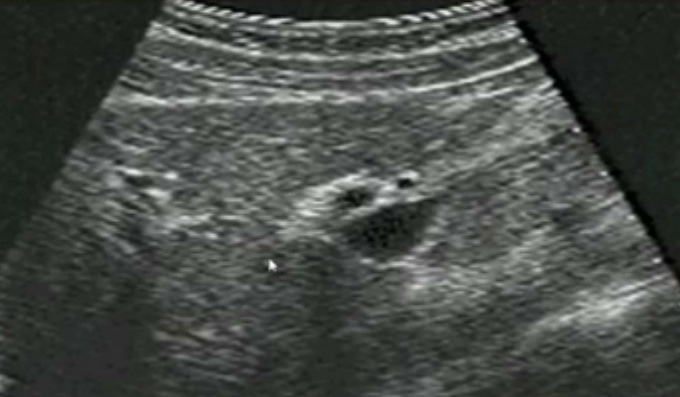

一、正常膽囊超聲圖像有的時(shí)候經(jīng)常發(fā)現(xiàn)檢查不到膽囊,其實(shí)有幾種可能性,檢查人員的技術(shù)不過(guò)關(guān)沒發(fā)現(xiàn)膽囊,就要找上級(jí)醫(yī)生會(huì)診,如果還是沒找到的話就不是技術(shù)問(wèn)題。結(jié)石或腫瘤充滿膽囊,使其液腔消失,慢性膽囊炎使得膽囊萎縮或膽囊壁肥厚而囊腔消失患者已進(jìn)食,膽囊處于膽汁排空的狀態(tài),膽囊先天性過(guò)小或缺失;膽囊位置極端異常(可能很低或位于左側(cè))膽囊切除術(shù)后(注意詢問(wèn)病史)。